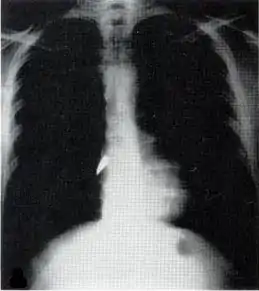

Рентгеновский снимок, показывающий пулю (белое пятно) в сердце

Большинство проникающих травм являются ранениями в грудную клетку и имеют уровень смертности менее 10 %[14]. Проникающее ранение грудной клетки может повредить жизненно важные органы, такие как сердце и лёгкие, и может помешать дыханию и кровообращению. Травмы лёгких, которые могут быть вызваны проникающим ранением, включают разрыв лёгочной артерии (порез или разрыв), ушиб легкого, гемоторакс (скопление крови в грудной полости за пределами легкого), пневмоторакс (скопление воздуха в грудной клетке) и гемопневмоторакс (скопление как крови так и воздуха в грудной клетке). Могут возникнуть сосательные раны на груди и натяжение пневмоторакса .

Проникающее ранение может также вызвать травмы сердца и системы кровообращения. Когда сердце пробито, оно может обильно кровоточить в грудную полость, если мембрана вокруг него (перикард) значительно разорвана, или может вызвать тампонаду перикарда, если перикард не разрушен[15]. В перикардиальной тампонаде кровь выходит из сердца, но задерживается внутри перикарда, поэтому между перикардом и сердцем нарастает давление, сжимая сердце и мешая его работе. Переломы рёбер обычно вызывают проникающее ранение грудной клетки когда острая кость прокалывает ткани.